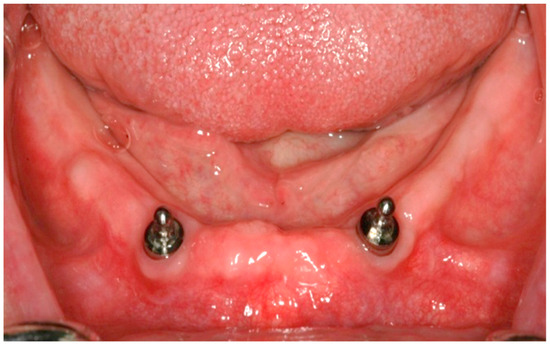

2.2. Surgical Treatment

2.3. Prosthetic Treatment